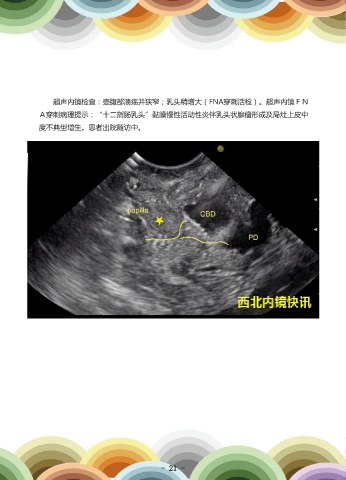

患者男,45岁,因“腹痛伴发热1天”就诊。患者因“胆囊切除术+胆总管探查术”                                         超声内镜检查:壶腹部溃疡并狭窄;乳头稍增大(FNA穿刺活检)。超声内镜FN

后T管拔除后出现腹痛、腹胀,发热就诊,胰腺CT示:胆总管末端软组织影,低位胆道                                         A穿刺病理提示:“十二指肠乳头”黏膜慢性活动性炎伴乳头状腺瘤形成及局灶上皮中

梗阻,胰管管腔扩张,考虑肿瘤性病变。                                                              度不典型增生。患者出院随访中。